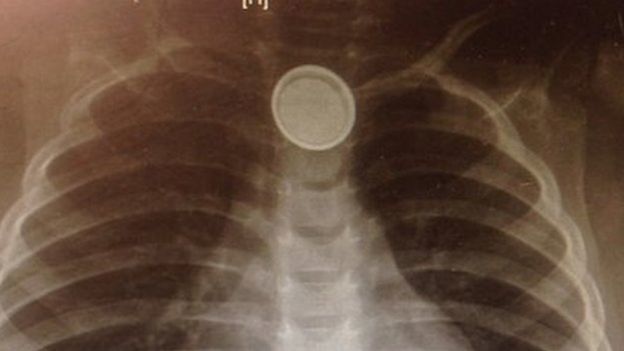

Pin cúc áo - 'sát thủ tý hon' trong nhà

Nhiều người không ngờ pin cúc áo - loại pin phổ biến trong nhiều loại đồ chơi, điều khiển từ xa và thiết bị điện tử gia dụng - lại là một "sát thủ" khiến không ít trẻ tử vong do không may nuốt phải chúng.